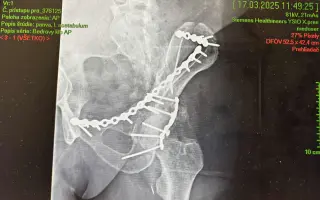

Volám sa Peter a 13. januára 2025 sa mi úplne zmenil život. Cestou pešo do práce ma zrazilo menšie nákladné auto z Česka. V priebehu sekundy som sa stal práceneschopným, pacientom s ťažkou polytraumou a trvalými následkami, lebo mi náraz zlomil panvu. Po nehode som bol hospitalizovaný takmer dva mesiace. Podstúpil som štyri operácie panvy a acetabula, ošetrenie poškodených nervov a dlhú pooperačnú rekonvalescenciu ktorú som ukončil koncom októbra 2025. Napriek všetkej liečbe mi zostali vážne zdravotné a psychické následky, ktoré ma významne obmedzujú v každodennom živote:

• Zlomenina acetabula (jamka bedrového kĺbu) – po opakovaných operačných stabilizáciách

• Zlomenina panvy – komplikovaná, s nutnosťou viacerých operácií

Pozrite si video zlomeniny mojej panvy, ktoré bolo urobené po nehode v nemocnici kde som bol hospitalizovaný.